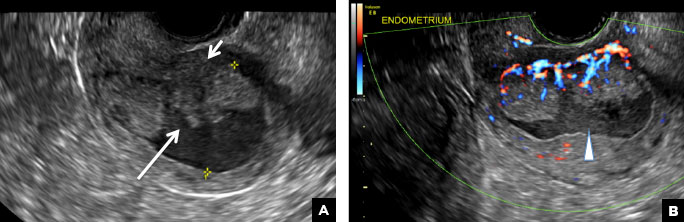

B) Submucosal fibroid CORRECT

Submucosal fibroids on ultrasonography appear as heterogeneous hypoechoic lesions distorting the endometrial cavity.1 In contrast to endometrial polyps, which involve the endometrium only, submucosal (intracavitary) fibroids originate in the myometrium, as clarified in Figures 3A & B. SHG demonstrates a broad-based mixed hypoechoic/isoechoic lesion protruding into the endometrial canal but preserving the echogenic endometrium, distinguishing myometrial from endometrial lesions. Submucosal fibroids often distort the endometrial myometrial interface and demonstrate acoustic shadowing.2,3

Submucosal fibroid. (A) Transvaginal pelvic ultrasound with color Doppler demonstrates a heterogeneous hypoechoic/isoechoic lesion arising from the myometrium (long arrow) and distorting the endometrial cavity. (B) SHG demonstrates a broad-based hypoechoic lesion protruding into the endometrial canal with areas of acoustic shadowing (arrowhead) but preserving the echogenic endometrium (short arrow).